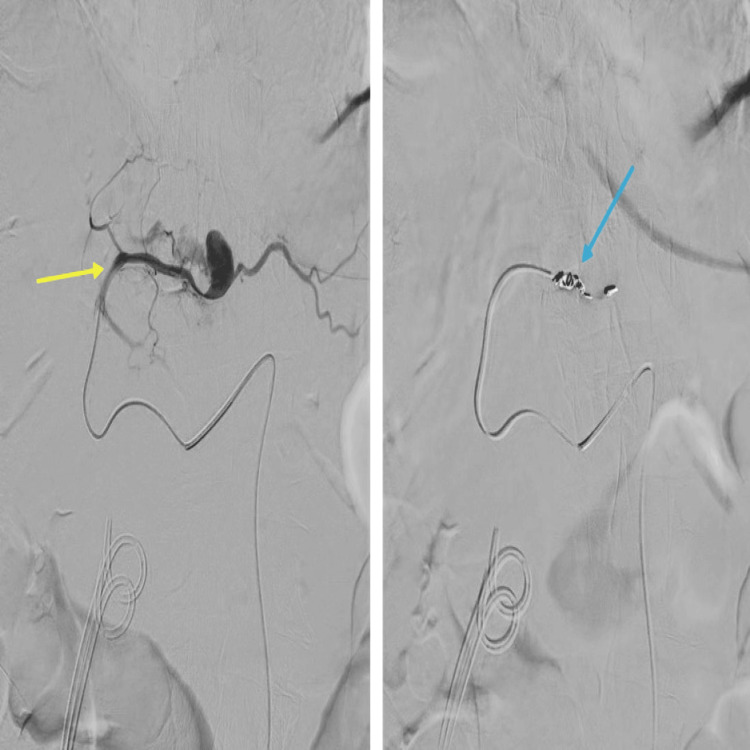

She was started on intravenous proton pump inhibitors (PPI) and underwent a CT of the abdomen and pelvis along the coeliac-mesenteric axis that suggested a 1.5 cm pseudoaneurysm arising from one of the segmental branches of the hepatic artery along segment 2 of the liver.

The patient underwent embolization of the left hepatic artery pseudoaneurysm by the interventional radiology team via a retrograde right common femoral artery (CFA) puncture. The CT angiogram along the coeliac-mesenteric axis confirmed a pseudoaneurysm from the segmental branch of the hepatic artery along segment 2 of the liver. This was selectively cannulated with a prograde catheter. The feeding vessel was successfully embolized with 4 mm coils, and no filling of the pseudoaneurysm was seen post-embolization (Figure 5).